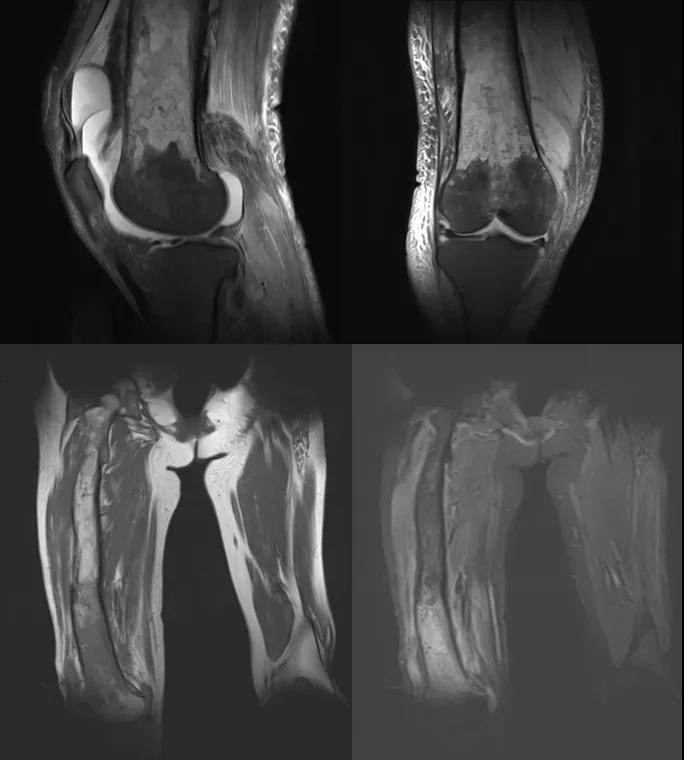

术前膝关节MRI和股骨MRI

面对如此复杂的病情,常规手术方案风险极高:患者股骨已严重畸形、骨皮质菲薄如纸,若强行清创固定,极可能在术后康复过程中发生病理性骨折;而长期慢性感染又导致其营养状况差、血小板异常升高,难以耐受大型手术。如何在控制感染、清除病灶的同时,最大限度保留膝关节功能、避免灾难性并发症?这成为摆在医疗团队面前的一道难题。